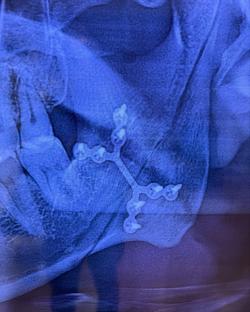

Darren is best known as his singer of Savage GardenIn an Instagram post on Friday, Darren shared pictures of his badly swollen and bruised face and neck, alongside an X-Ray showing metal plates on the inside of his face.

Getting reconstructive surgery four days later, the I Knew I Loved You singer was fitted with a titanium brace to reconnect his jawbone. His mouth was then wired shut for eight weeks.